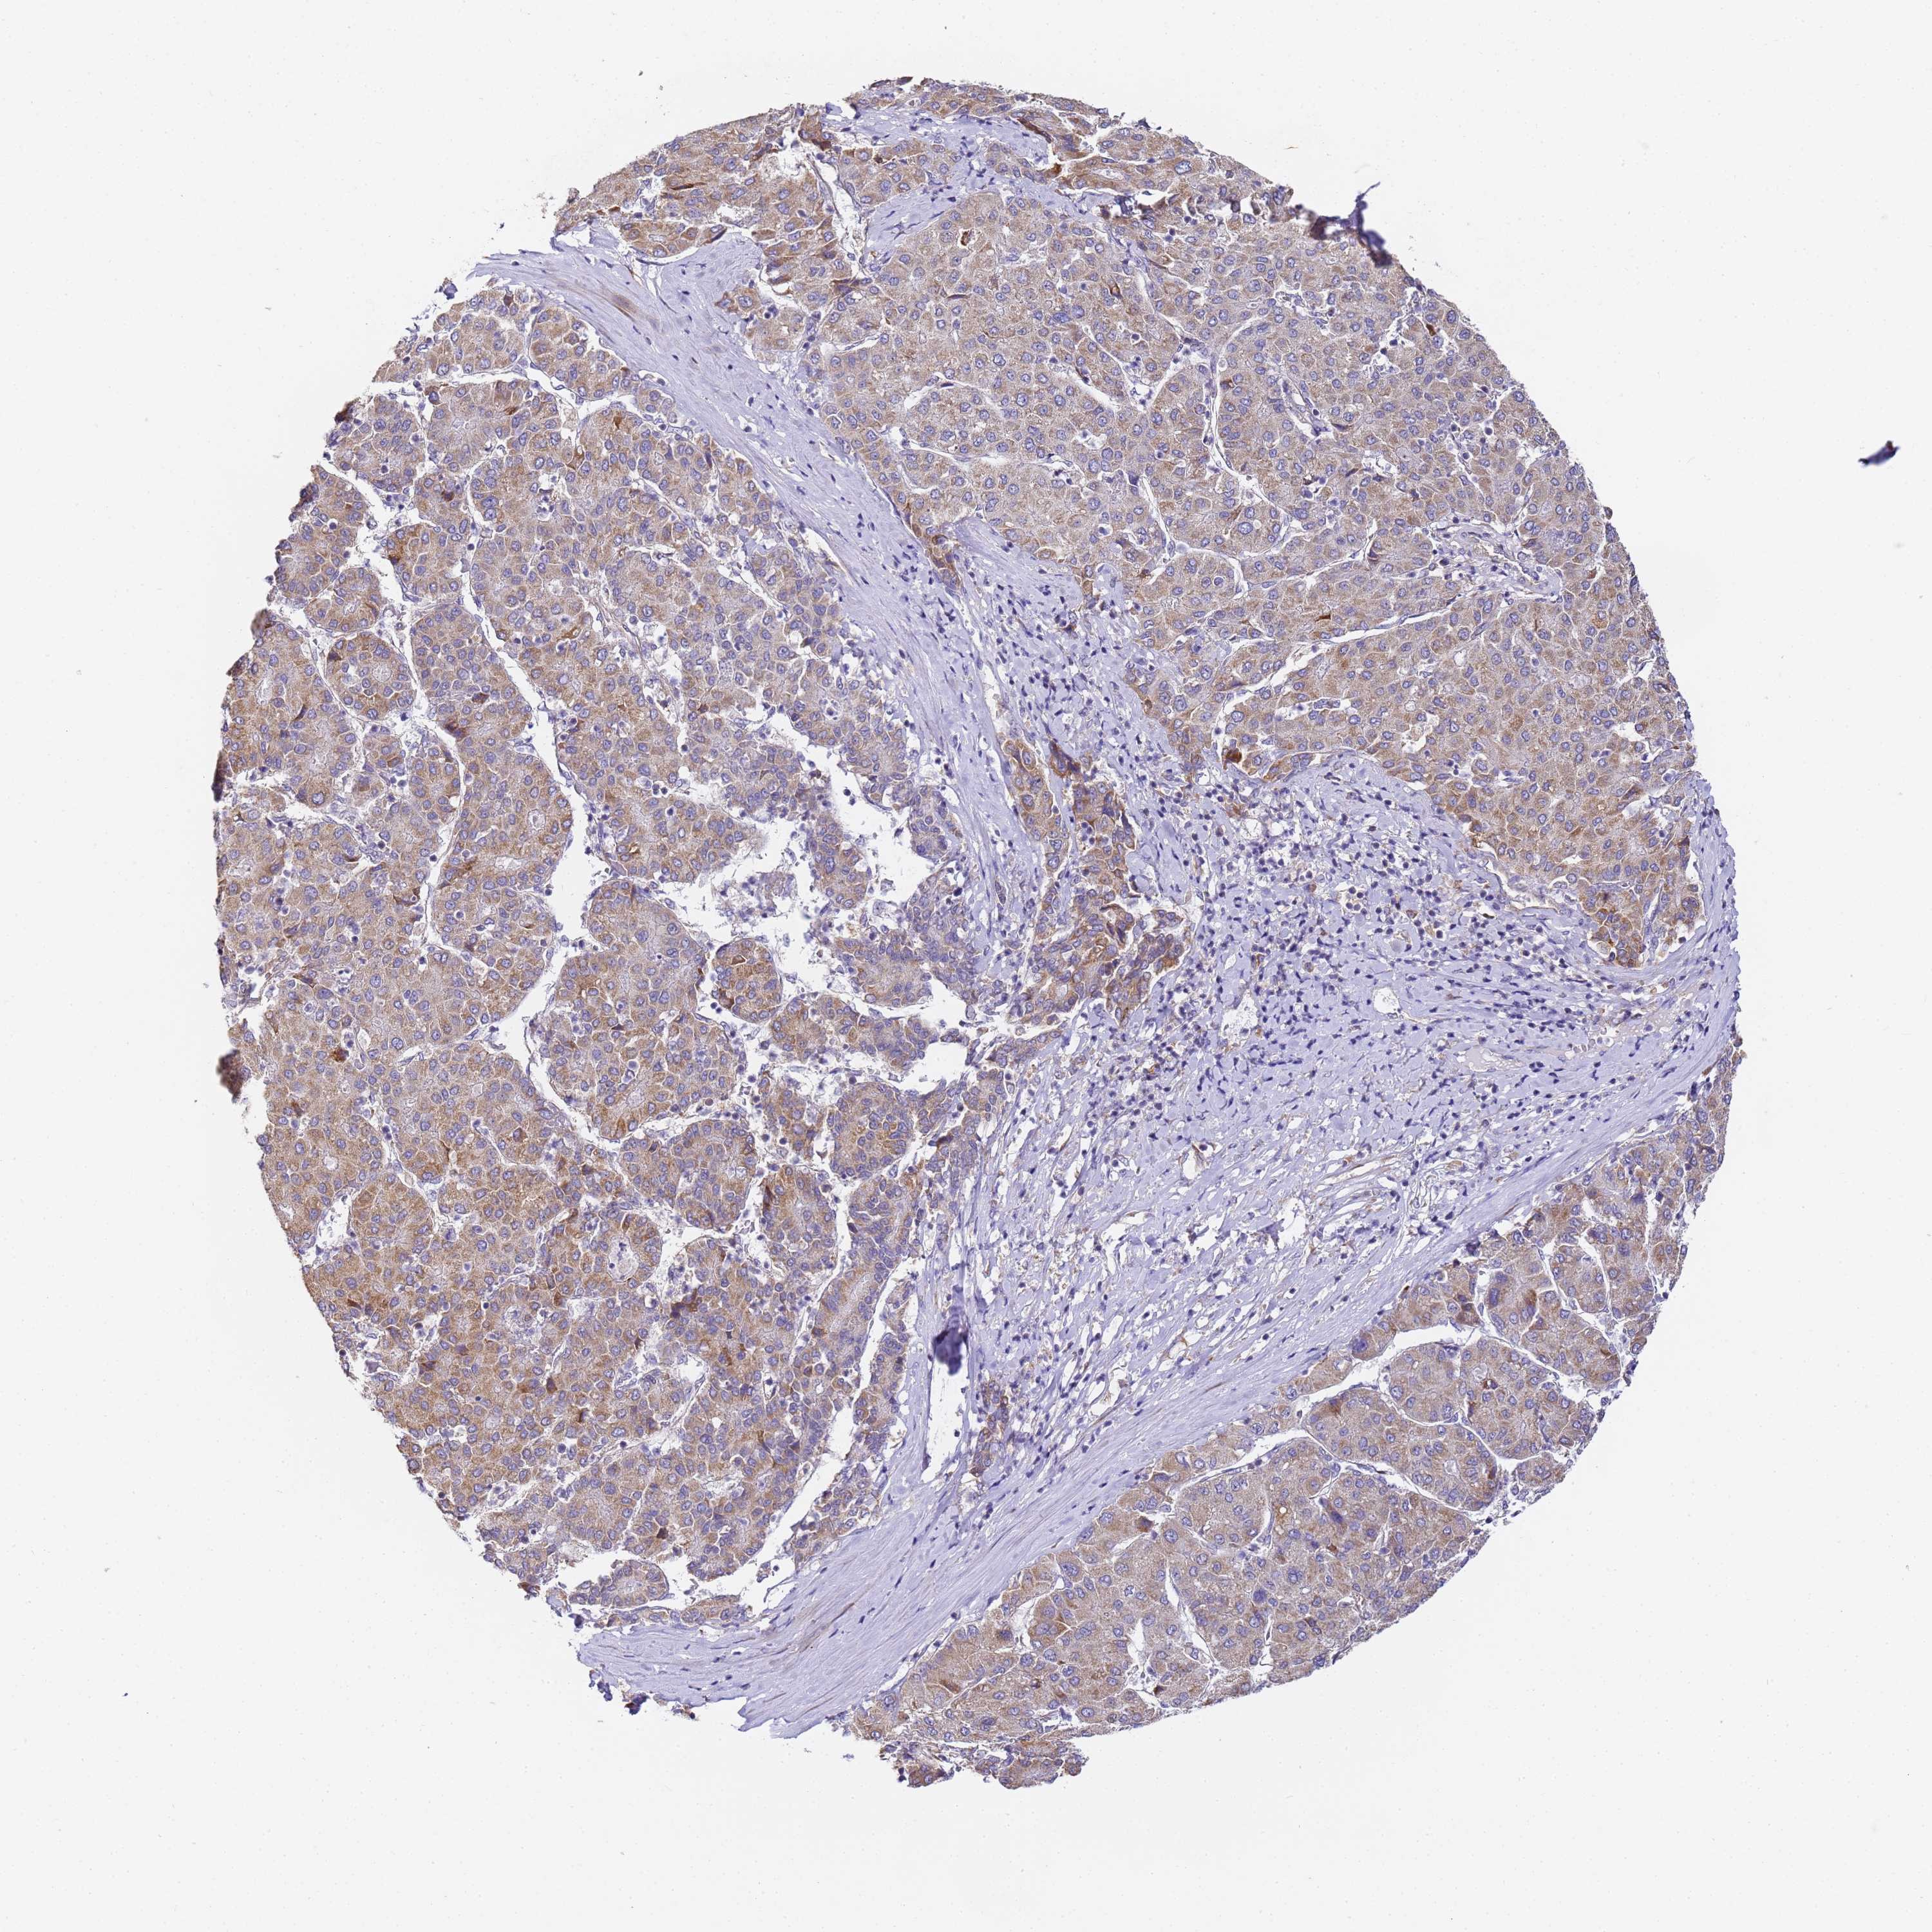

LIVER CANCER - Protein expressioni

A mouse-over function shows sample information and annotation data. Click on an image to view it in a full screen mode. Samples can be filtered based on level of antibody staining by selecting one or several of the following categories: high, medium, low and not detected. The assay and annotation is described here.

Note that samples used for immunohistochemistry by the Human Protein Atlas do not correspond to samples in the TCGA dataset.

Antibody stainingi

Antibody staining in the annotated cell types in the current human tissue is reported as not detected, low, medium, or high, based on conventional immunohistochemistry profiling in selected tissues. This score is based on the combination of the staining intensity and fraction of stained cells.

Each image is clickable and will lead to virtual microscopy that enables deeper exploration of all samples and also displays staining intensity scores, fraction scores and subcellular localization as well as patient and tissue information for each sample.

Antibody HPA038751

Staining

High

Medium

Low

Not detected

Intensity

Strong

Moderate

Weak

Negative

Quantity

>75%

75%-25%

<25%

None

Location

Nuclear

Cytoplasmic/membranous

Cytoplasmic/membranous,nuclear

Cholangiocarcinoma

Carcinoma, Hepatocellular, NOS